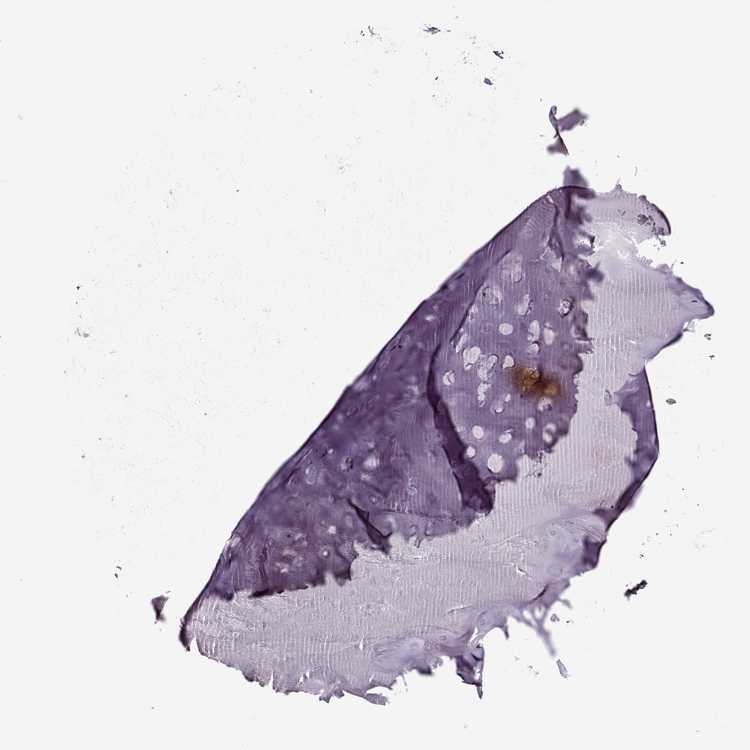

SOFT TISSUE 1 - Antibody stainingi

Antibody staining in the annotated cell types in the current human tissue is reported as not detected, low, medium, or high, based on conventional immunohistochemistry profiling in selected tissues. This score is based on the combination of the staining intensity and fraction of stained cells.

Each image is clickable and will lead to virtual microscopy that enables deeper exploration of all samples and also displays staining intensity scores, fraction scores and subcellular localization as well as patient and tissue information for each sample.

Antibody HPA041047

Chondrocytes Not detected

Fibroblasts Not detected

SOFT TISSUE 2 - Antibody stainingi

Peripheral nerve Not detected